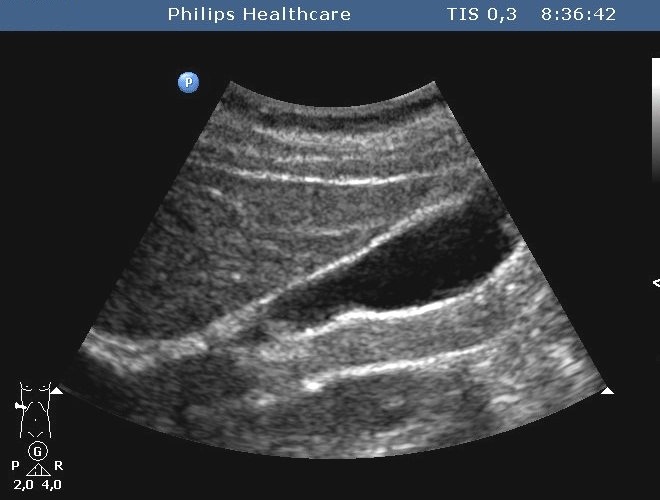

The bacteria may pile up in the biliary ducts due to the bile stasis (either by tumorous or inflammatory choledochus compression) and cholangitis can develop, associated with an abscess development later (Figure 29).

In order to prevent it – by either endoscopically or percutaneously – the primary goal is to ensure the bile flow again, obviously completed with broad-spectrum antibiotics.

Liver abscess can develop either following the severe inflammation of the biliary ducts and the gallbladder or following a tumorous necrosis or by the spread of an external inflammation to the liver. By the help of the US, a cystic lesion can be seen with multiple internal echos containing gas bubble frequently as well. In order to determinate the further therapy, contrast enhanced CT examination can be needed, if the US imaging of the entire liver was not possible. An avascular intrahepatic lesion can be seen well on the CT with a contrast enhancing wall (sometimes multifocal as well) (Figure 30). An US or CT guided percutaneous drainage can provide a therapeutic result depending on the lesion's size and location (Figure 31).

Figure 30: Abscess in the liver, native CT

Figure 31: Abscess in the liver, US control after US guided drainage